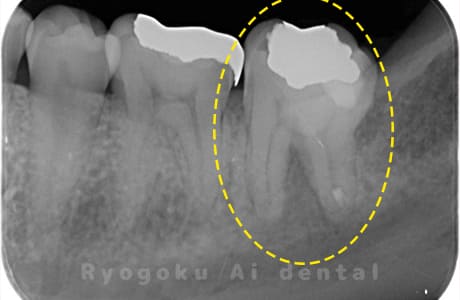

Case04

-

- 原因

- 歯根嚢胞

- 治療内容

- 歯根端切除法

- 治療費用

- ¥110,000

他院で治療した歯が腫れていて、様子を見るように言われたが、なかなか治らない、とのことでご来院された患者さんです。歯根端切除術を行い、腫れもなくなり、経過良好です。

<リスク・副作用>

外科手術のため、術後に出血、痛みや腫れ、違和感を伴います。口腔内の状態によっては適応できないことがあります。歯根端切除で治らなければ抜歯を検討しなくていけない場合もあります。